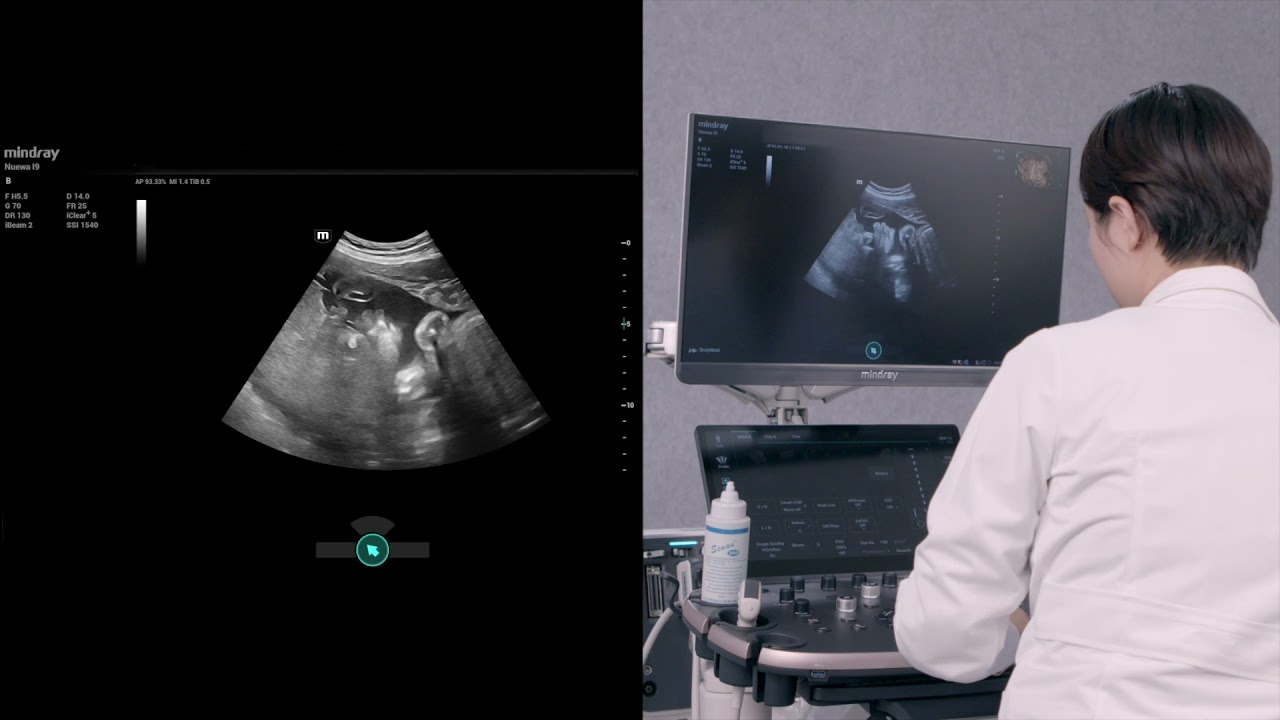

Unsere L?sungen zur Bildgebung orientieren sich am Bedarf der ?rzte und des Pflegepersonals, sowie am Wohl der Patienten. Wir verfolgen damit das Ziel, genauere Diagnosen und eine zuverl?ssige Behandlung in verschiedensten medizinischen Bereichen zu erm?glichen.

Optimierte OBG-Workflows sind n?tig, wenn gro?e Patientinnenzahlen im Rahmen von Gesundheitsscreenings bew?ltigt werden sollen. Zum Beispiel sind Fehlbildungen des zentralen Nervensystems (ZNS) eine der h?ufigsten angeborenen Anomalien. Wegen verschiedener f├╝r die Bildgebung ung├╝nstiger Bedingungen, etwa eine schwierige Position des F?tus, ist es besonders schwer, die MSP von 2D-Ultraschall zu erhalten. Aus diesem Grund k?nnen automatisierte Erkennung und Messungen die Scanning-Effizienz deutlich steigern.

Infolge des Coronavirus haben Krankenh?user und Gesundheitspersonal neue Arbeitsweisen entwickelt, etwa, in Akutbereichen, Social Distancing, strikte Pflicht zum Tragen einer Maske oder anderer pers?nlicher Schutzausr├╝stung (PSE), H?nde waschen und t?gliches Desinfizieren der Ausr├╝stungsgegenst?nde. Tragbare, hochmobile und vielseitige Ger?te kamen f├╝r den Point-of-care (POC) insbesondere dann in den Blick, wenn Stationen und Operationss?le ├╝ber zahlreiche Stockwerke verteilt lagen und der Zugang zu Spezialger?ten schwierig war.